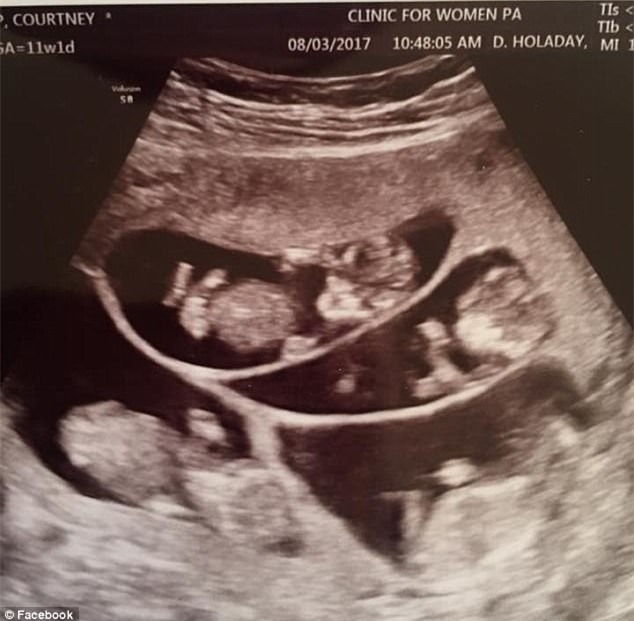

Hình ảnh siêu âm của chị Courtney. (Ảnh: dailymail)

Khi mang thai được 11 tuần, chị Courtney chia sẻ trên trang cá nhân rằng, mối quan tâm lớn nhất của chị khi đó là lượng calorie nạp vào bởi chị được yêu cầu phải nạp vào cơ thể một lượng lớn để đủ cho chị và 6 đứa bé phát triển khỏe mạnh.